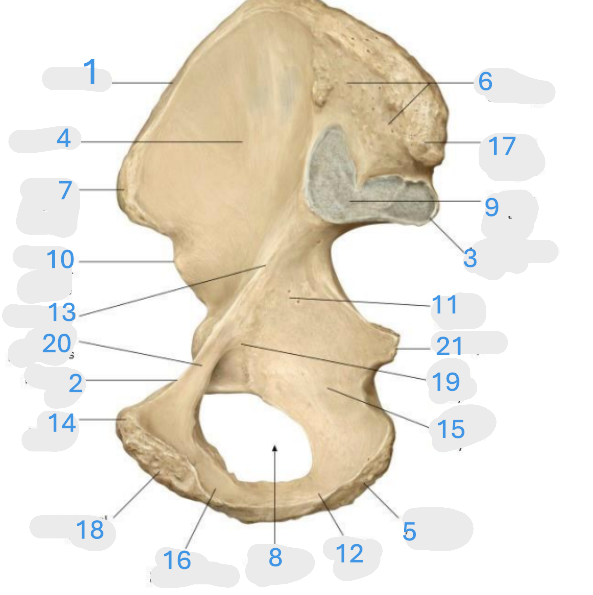

Where is the iliac crest

1

Where is the pectineal line

2

Where is the posterior iliac spine

3

Where is the iliac fossa

4

Where is the ischial tuberosity

5

Where is the iliac tuberosity

6

Where is the anterior superior iliac spine

7

Where is the obturator foramen

8

Where is the auricular surface of the ilium

9

Where is the anterior inferior iliac spine

10

Where is the ilium body

11

Where is the ischial ramus

12

Where is the arcuate line

13

Where is the pubic tubercle

14

Where is the ischium body

15

Where is the inferior pubic ramus

16

Posterior superior iliac spine

17

Where is the symphyseal surface

18

Where is the pubis body

19

Where is the superior pubic ramus

20

Where is the ischium body

21